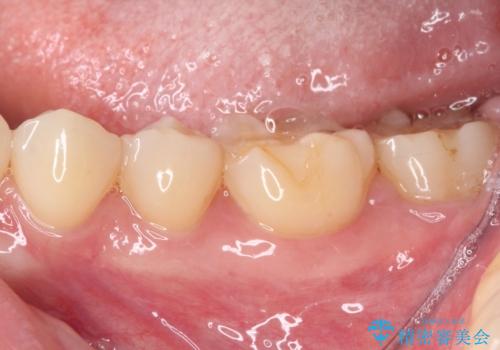

- 左下の奥歯が、冷たいものを食べるとしみて、舌で触るとザラザラすることが気になり来院された患者様です。

以前他院で治療したCR(樹脂の材料)が劣化し、その隙間から冷たいものがしみている可能性が高いことがわかりました。

嚙み合わせの力が強いため、再びCRやセラミックインレーによる修復を行っても割れてしまう可能性が高いので、

ゴールドインレーによる修復を行うこととしました。